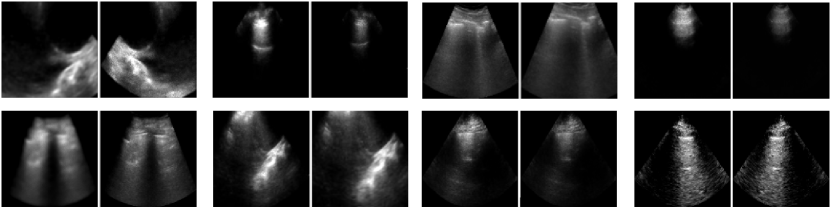

3.3 Self-Supervised Pretraining

Three Joint Embedding SSL methods were trialled to produce pretrained models for each LUS tasks: SimCLR (with τ=0.1𝜏0.1\tau=0.1[9], Barlow Twins (with γ=0.005𝛾0.005\gamma=0.005[10], and VICReg (with γ=25𝛾25\gamma=25, μ=25𝜇25\mu=25, ν=1𝜈1\nu=1[11]. As was done in the original studies, positive pairs were produced by distorting images by applying stochastic data augmentations sampled from a family of transformations. Figure 3 provides examples of augmented view of B-mode images from the local dataset. Below is the list of transformations, where P𝑃P indicates the probability of that transformation being applied:

1. 1.

Random crop of c𝒰(0.5,1.0)similar-to𝑐𝒰0.51.0c\sim\mathcal{U}(0.5,1.0) of the image’s area. (P=0.8𝑃0.8P=0.8).

2. 2.

Horizontal flip. (P=0.5𝑃0.5P=0.5)

3. 3.

Multiplicative Gaussian noise, with SD

σ𝒰(0.0,0.1)similar-to𝜎𝒰0.00.1\sigma\sim\mathcal{U}(0.0,0.1). (P=0.5𝑃0.5P=0.5).

4. 4.

Brightness adjustment by c𝒰(0.5,1.5)similar-to𝑐𝒰0.51.5c\sim\mathcal{U}(0.5,1.5). (P=0.7𝑃0.7P=0.7).

5. 5.

Contrast adjustment by c𝒰(0.6,1.0)similar-to𝑐𝒰0.61.0c\sim\mathcal{U}(0.6,1.0). (P=0.7𝑃0.7P=0.7). With probability 0.50.50.5, this occurs before brightness adjustment.

Refer to caption

Figure 3: Augmented views of B-mode images, comprising positive pairs for self-supervised pretraining.